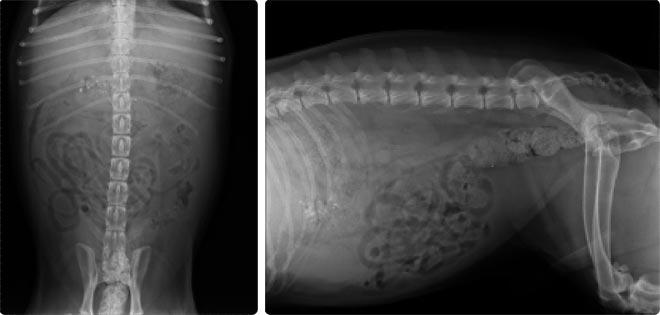

- Raio-x e/ou ecografia (para visualizar se mais órgãos estão afetados)

- Tomografia computorizada (TAC) ou ressonância magnética (RM) (em caso de suspeita de tumores malignos e metástases)